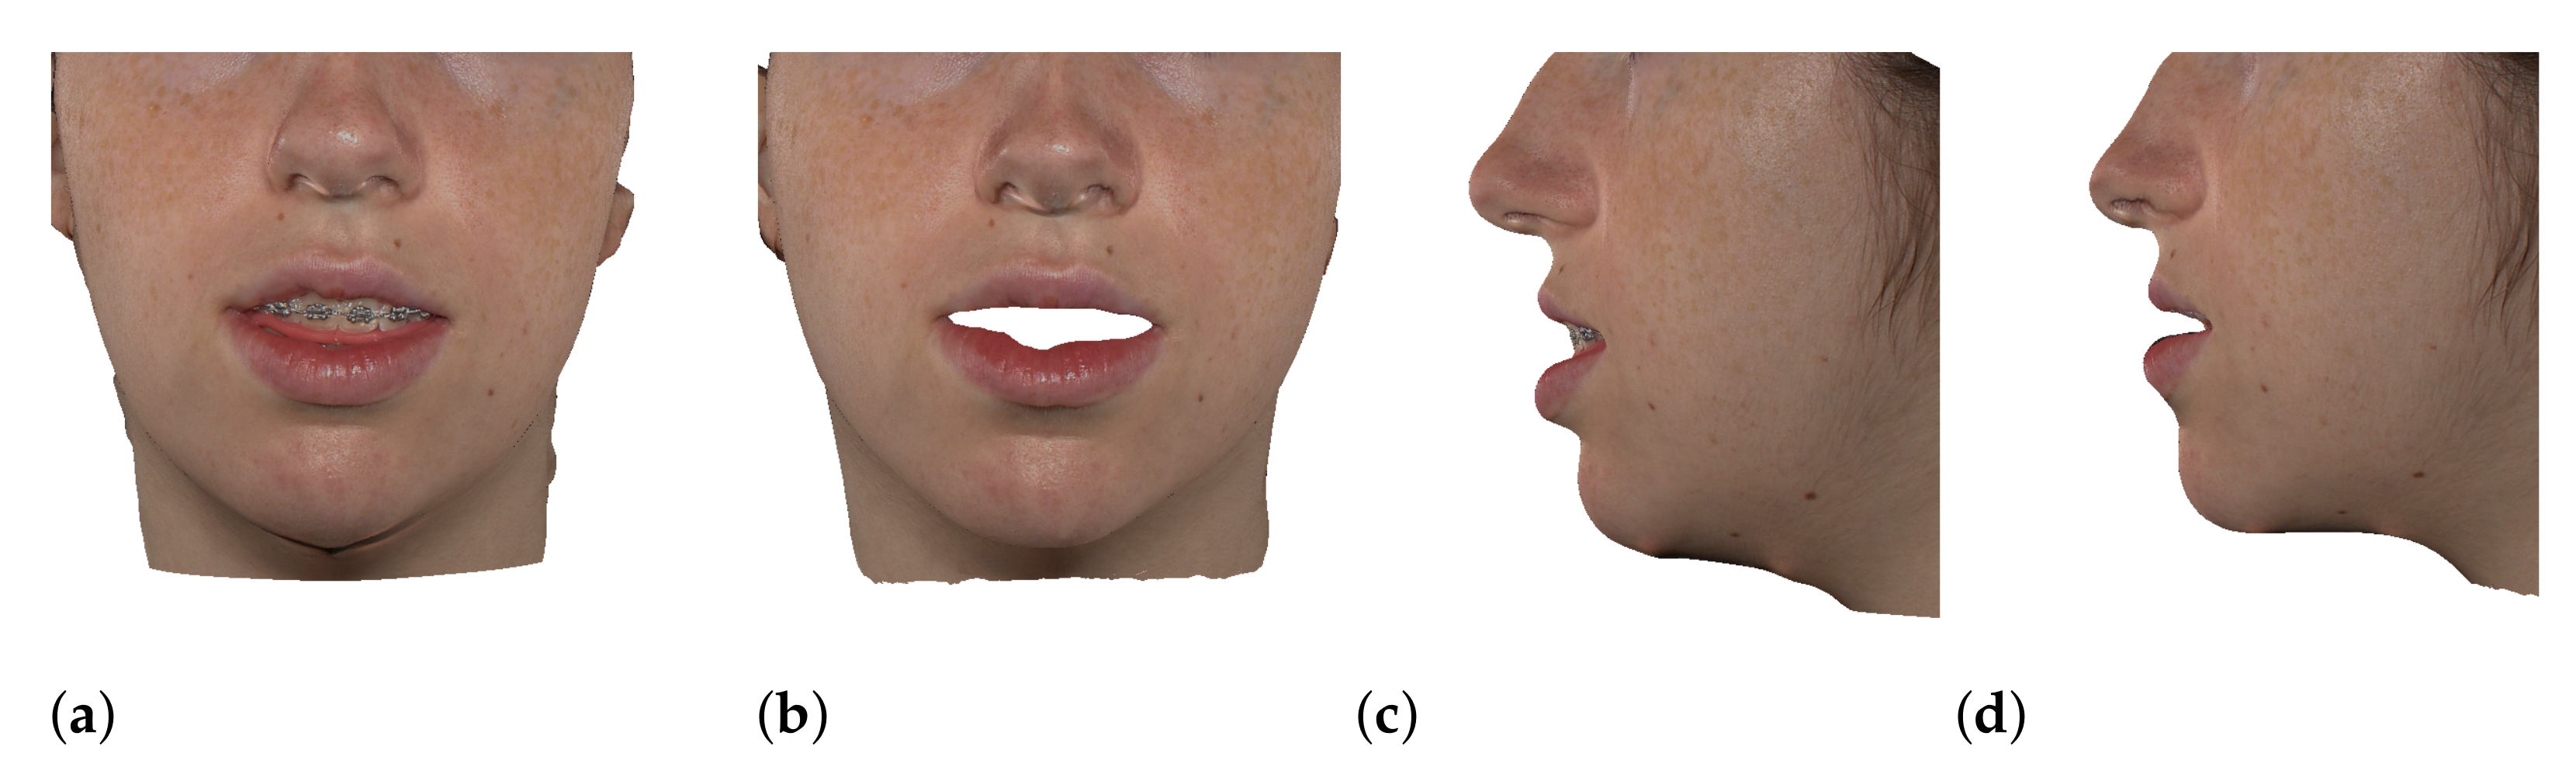

2.6. Textured Output Visualization

3.1. Validation Methodology

3.2. Test Cases